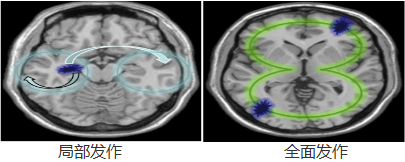

三、局限性发作,发病时表现为一侧口角、眼睑、手指、足趾或一侧面部及肢体末端短阵性抽搐或麻木刺痛。抽搐有时可由手指至上肢扩展到对侧。